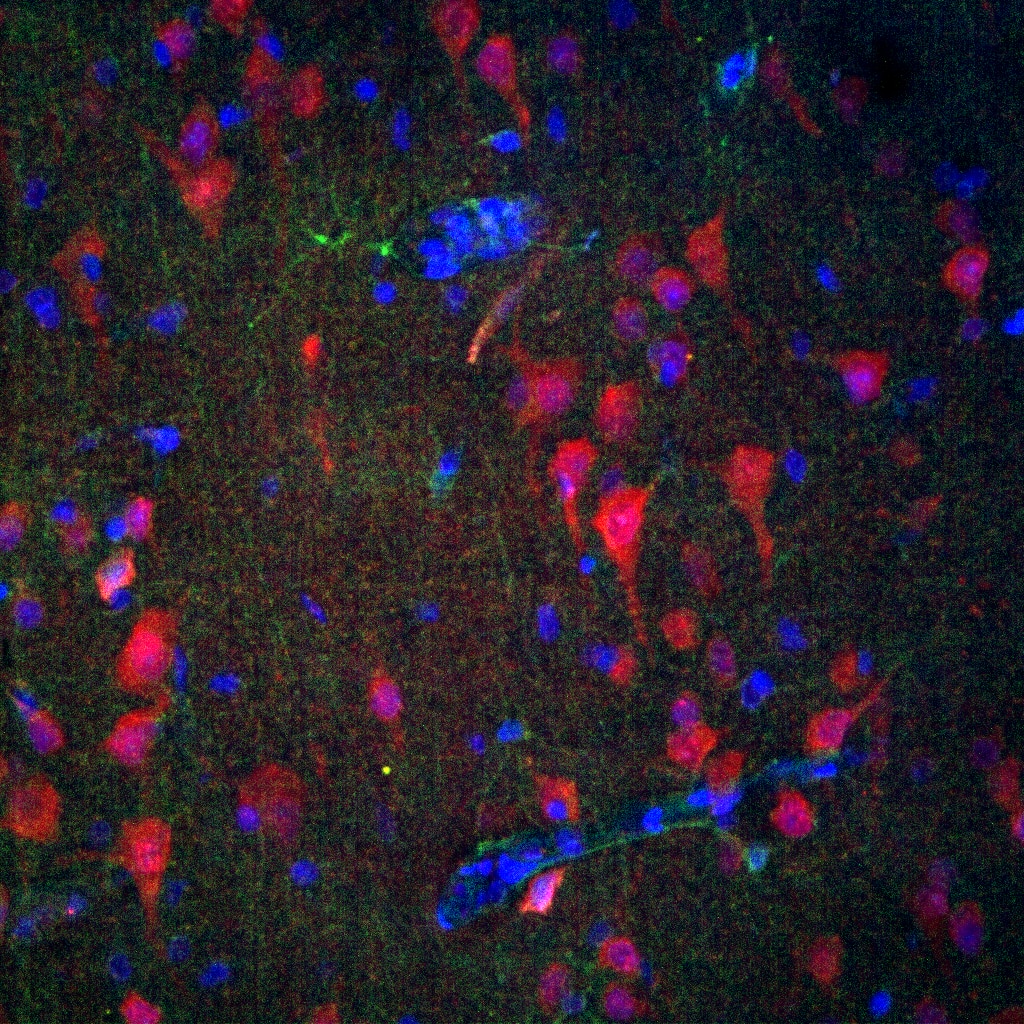

FH Reyes (Verified Customer) (09-24-2025) | phospho-MEK2 (in green) worked in human brain FFPE tissue, marking spefically astrocytes in the TSC sample.

![]() |